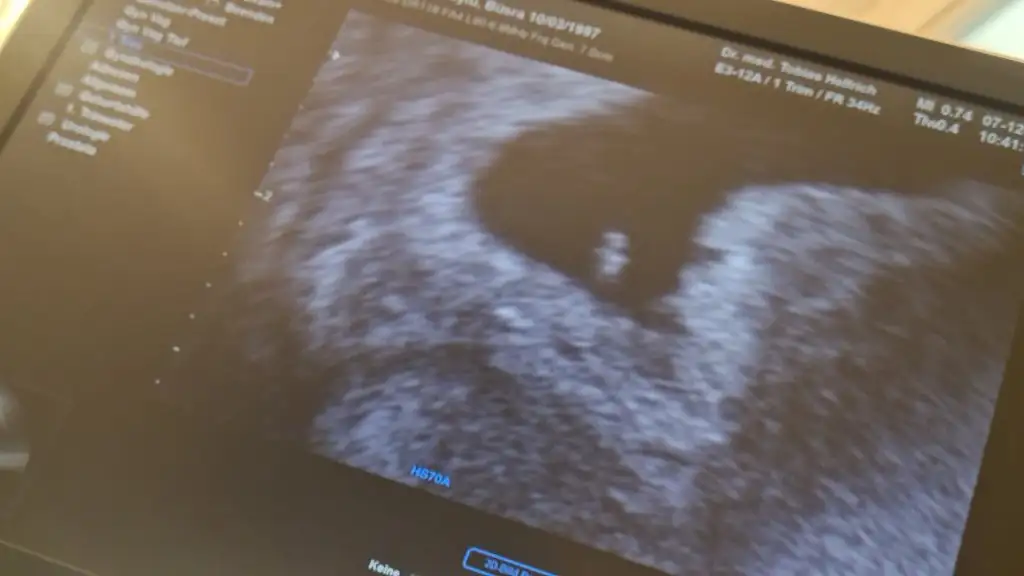

6+1 resim böyle. ☺☺☺ gidecek olanlara bi fikir olur belki. Benimle ayni haftada olan varmi 6 haftalikBenimkide bukücük mercimegim benim. 0,32 mm ymis. Kizlar insallah hepiniz kucaginiza alirsiniz bende dahil.

6 haftalıkta kalp atışı duyulmuyor mu sen duymussundjd6+1 resim böyle. ☺☺☺ gidecek olanlara bi fikir olur belki. Benimle ayni haftada olan varmi 6 haftalik

Oy maşallah süphanallah ne güzel gözünüz aydınBenimkide bukücük mercimegim benim. 0,32 mm ymis. Kizlar insallah hepiniz kucaginiza alirsiniz bende dahil.